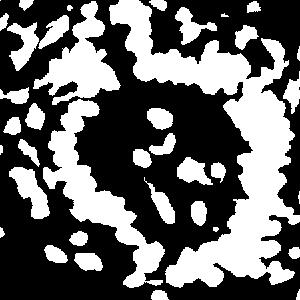

(a) image

(b) round 1

(c) round 2

(d) round 3

An example is shown in Fig. 2 to illustrate the masks in different rounds of self-training. The foreground nuclei annotation (green pixels) is kept unchanged during the iterations while the background area (pixels in black) grows up gradually. In the third round, the background has high accuracy and the ignored pixels (orange) are almost all nuclei.